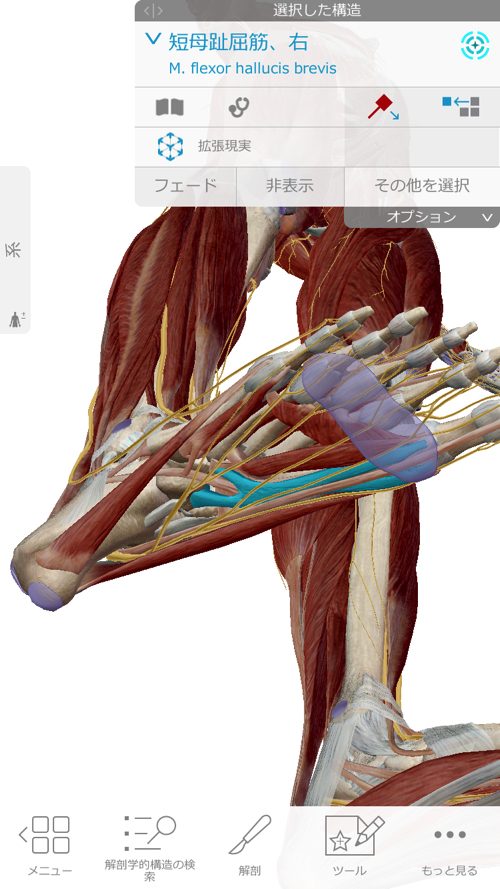

腓骨筋の先には親指を動かす短母趾屈筋

同じく趾に影響の大きい母趾内転筋にも連携しています。

長腓骨筋は膝・足首・足裏・足の指に全て影響するのがお分かり頂けたと思いますが